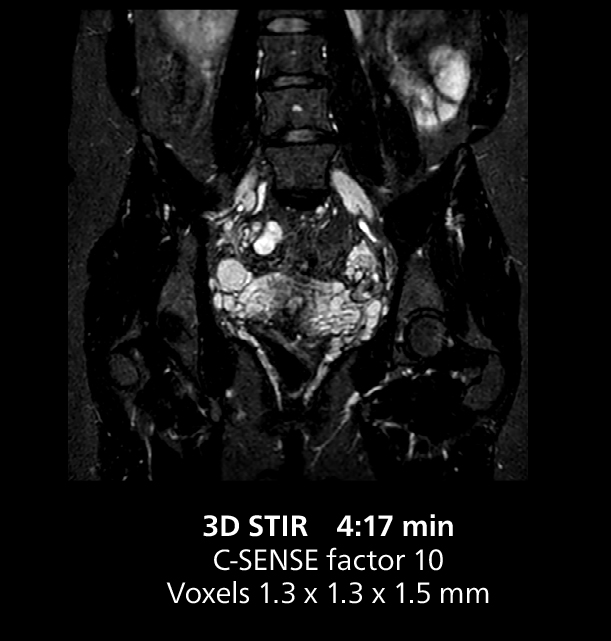

Le Dr Gellée estime que la fiabilité des acquisitions en respiration libre est “la caractéristique qui fait la plus grande différence au quotidien. Les séquences 3D en respiration libre sont très reproductibles et l’acquisition axiale est très bonne. Par exemple, pour l’endométriose, qui est l’un de mes domaines de prédilection, elles offrent un contraste élevé et une bonne résolution, ce qui me permet de voir les moindres détails. Nous utilisons également la respiration libre pour l’imagerie du foie et du pancréas. Dans les examens du foie multiphases, la respiration libre 4D offre une résolution temporelle de 3 secondes, permettant une acquisition dynamique avec plusieurs phases artérielles.”

Cet exemple comprend une IRM 3D en respiration libre et une IRM dynamique 4D en respiration libre d’un foie métastasé. Une séquence FatSat de haute qualité avec une bonne résolution est produite en 1 min et 36 s avec MultiVane XD pondéré en T2.

Cet exemple d’IRM illustre une bonne résolution et une bonne qualité d’image obtenue avec des temps d’acquisition raisonnables à l’aide du système MR 5300 1.5T avec l’antenne antérieure TorsoCardiac qui permet d’utiliser un champ d’acquisition étendu.